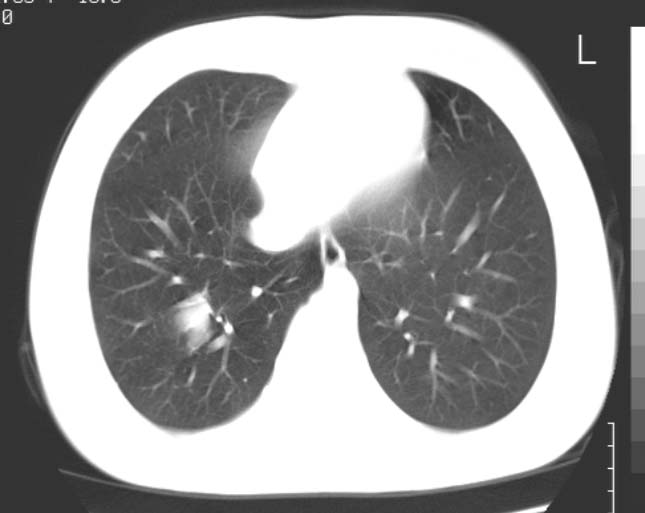

标题: CT25816:胸部CT,请会诊。

女 19岁,发热,咳嗽

右肺下叶支扩伴感染。

考虑血管畸形。建议临床进一步检查。

考虑肺血管畸形可能性大,建议增强检查。或薄层ct后三维重建。

考虑右下肺动静脉畸形,建议增强进一步检查。